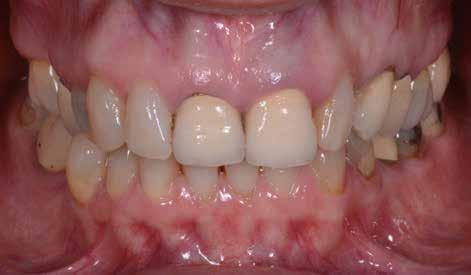

A fogorvosi beavatkozásokkal szemben támasztott követelmények között az utóbbi időben egyre hangsúlyosabbá vált az attraktív esztétikai eredmények elérése iránti igény. Ezzel párhuzamosan a páciensek egyre jelentősebb hányada igényli a minimálinvazív terápiás lehetőségek alkalmazását. Vannak azonban olyan esetek, ahol a beavatkozások megkezdése előtt fennálló kiindulási állapot különböző előkezelések elvégzését teszik szükségessé annak érdekében, hogy az ellátás eredményeként minimálinvazív módszerekkel biztosított esztétikus megjelenést tudjunk elérni. Az alábbiakban olvasható esetbemutatás során egy olyan multidiszciplináris funkcionális és esztétikai kezelést fogunk ismertetni, ahol minimálinvazív módszerek alkalmazása mellett tudtunk esztétikus eredményeket is elérni.

Az esztétikus végeredmények biztosítása érdekében gyakran multidiszciplináris megközelítés alkalmazására van szükség. Ezeket a több szakterületet is érintő beavatkozásokat ugyanaz a fogorvos is biztonsággal elvégezheti, ha a tervezett beavatkozások komplexitása nem igényli az adott szakterülettel kapcsolatos mély ismeretek meglétét. Ha nagyobb volumenű, vagy speciális ismereteket igénylő komplex kezelésekről van szó, akkor egyértelműen az adott területre vonatkozó szakvizsgával rendelkező specialista felkeresését javasoljuk. Az alábbi esetbemutatásban ismertetésre kerülő beavatkozásokat ugyanaz a fogorvos végezte. A beavatkozások elvégzése során mindvégig minimálinvazív módszereket alkalmazott.

A 26 éves férfi páciens azzal a kéréssel kereste fel a rendelőnket, hogy a frontfogai esztétikusabb megjelenését szeretné elérni. A páciens jó általános egészségi állapottal rendelkezett, nem szenvedett allergiáktól és nem kellett rendszeresen gyógyszereket szednie. A páciens lehetőség szerint kerülte a fogai megmutatását. Rendkívül zavarónak találta a nagymetszői között, a középvonalnak megfelelően látható rést, a fogain látható kopási jeleket, valamint a fogai méretét is túl kicsinek találta. A szájüregi vizsgálat során megállapítottuk, hogy a nagymetsző fogai (11, 21) élharapásban vannak, valamint az alsó fogíven kismértékű torlódást észleltünk. A felső frontfogakon

(13-23) attrícióra utaló jeleket találtunk. A fogak kopása a nagymetszőfogaknak megfelelően volt a legkifejezettebb (1. ábra) . Az előbbiekben említett fogak (11, 21) ezen kívül némileg elfordultak, és jelentősebb méretű diasztéma volt köztük. A páciens Angle I.-osztályú állcsontrelációs helyzettel rendelkezett. A vizsgálat során feltűnt, hogy a páciens csak nagyon óvatosan mert mosolyogni (2. ábra)

A szájüregi vizsgálat során nem találtunk szuvas léziók jelenlétére utaló eltéréseket. A nagymetszőfogakon megfigyelhető jelentős mértékű kopás ellenére nem észleltünk craniomandibuláris diszfunkció jelenlétére utaló jeleket. A vizsgálat befejezését követően a pácienst tájékoztattuk a különböző kezelési lehetőségekről. Az esztétikai megjelenés javítása érdekében először egy alignerekkel végzett fogszabályzó kezelés elvégzését, majd a harapási helyzet optimalizálását követően a felső frontfogai kompozittal történő direkt felépítését vagy héjakkal történő ellátását (pl.: non-prep héjak) javasoltuk (3. és 4. ábra).

Az alignerekkel történő fogszabályzó kezelés elvégzéséhez az Invisalign rendszert használtuk. Az orthodonciai kezelés során 14 sín került felhasználásra. A páciensnek minden egyes sínt 10 napon keresztül kellett viselnie. A fogszabályzó kezelés céljai között szerepelt az élharapás megszüntetése, a szemfogak derotálása, valamint az alsó fogíven látható torlódás feloldása.

Az orthodonciai terápia során a fogív tágításra került, és a fogak között látható rések is egyenletes módon lettek elosztva a frontfogak között. Erre azért volt szükség, hogy a restauratív fázis során lehetőségünk legyen a harmonikus szé-

lességű és hosszúságú fogformák kialakítására (5. ábra)

A labiális és bukkális fogfelszínekre helyezett attachmentek feleltek a sínek által a fogakra kifejtett erők megfelelő átvitelének biztosításáért. Az eset ellátása során végzett orthodonciai előkezelést funkcionális szempontból a protetikai vagy restauratív célú fogászati beavatkozások közé sorolhatjuk. Ebben az esetben az orthodonciai beavatkozásnak az volt a célja, hogy lehetővé tegye a definitív fogpótlások minimálinvazív módon történő elkészítését. Az alignerekkel történő fogmozgatások befejezését követően a pácienst egy felső retenciós sínnel láttuk el. Az alsó fogíven az elért eredmények stabilitását fix retainer felhelyezésével biztosítottuk.

A kezelések második fázisában a pácienssel közösen non-prep/ minimálinvazív héjak készítése mellett döntöttünk (6. és 7. ábra).

Az ilyen jellegű ellátás során csupán a lehető legkisebb mennyiségű foganyag kerül eltávolításra. A minimálinvazív beavatkozás elvégzését lehetővé tevő feltételeket a fogszabályzó kezelés során alakítottuk ki. A fogazat minimálinvazív módon készített héjakkal történő ellátásához a fogaknak olyan pozícióban kell lenniük, amely lehetővé teszi az esztétikai megjelenés additív eljárások alkalmazása mellett történő optimalizálását. Azonban az ellátás során előbbiekben felsoroltakon kívül más szempontokat is figyelembe kell vennünk. Amennyiben a páciens a jelenleg látható fogszínéhez képest jelentős változást szeretne elérni, úgy sokkal vastagabb héjak készítésére van szükség, és az ezáltal megnövekedett helyigény miatt sok esetben nincs lehetőség kizárólag additív eljárások alkalmazására (8. ábra). Mivel a cikkben bemutatásra kerülő eset ellátása során a fogazat helyzeti rendellenességei az előzetes orthodonciai kezelés keretei között korrekcióra kerültek, ezért lehetőségünk adódott a restauratív fázis minimálinvazív módon történő elvégzésére. Az általunk alkalmazott terápia hátrányai között szerepelt, hogy az elvégzett beavatkozások időigénye miatt a tervezett végeredményt csupán viszonylag hosszú idő után tudtuk elérni.

A páciens teljesen elégedett volt a kezelések befejezését követően elért esztétikai végeredménnyel (9. ábra). A terápiás erőfeszítéseink eredményeinek köszönhetően újra képes felszabadultan nevetni és mosolyogni. A cikkben bemutatásra kerülő eset jól példázza a multidiszciplináris beavatkozások alkalmazásában rejlő előnyöket. A megfelelő sorrendben végzett orthodonciai és restauratív kezelésekkel lehetővé vált a páciens mosolyának minimálinvazív módszerekkel történő optimalizálása. A körültekintő tervezésnek köszönhetően nem került sor felesleges beavatkozások elvégzésére, és emiatt a kezelések befejezéséhez szükséges idő sem nyúlt a szükségesnél hosszabbra. Arra is felhívnánk a figyelmet, hogy a jól megszervezett, továbbá a lehető legkevesebb rendelési időt felhasználó kezelések – a beavatkozásokat végző fogorvosok számára is – rendkívül kedvezőek lehetnek.